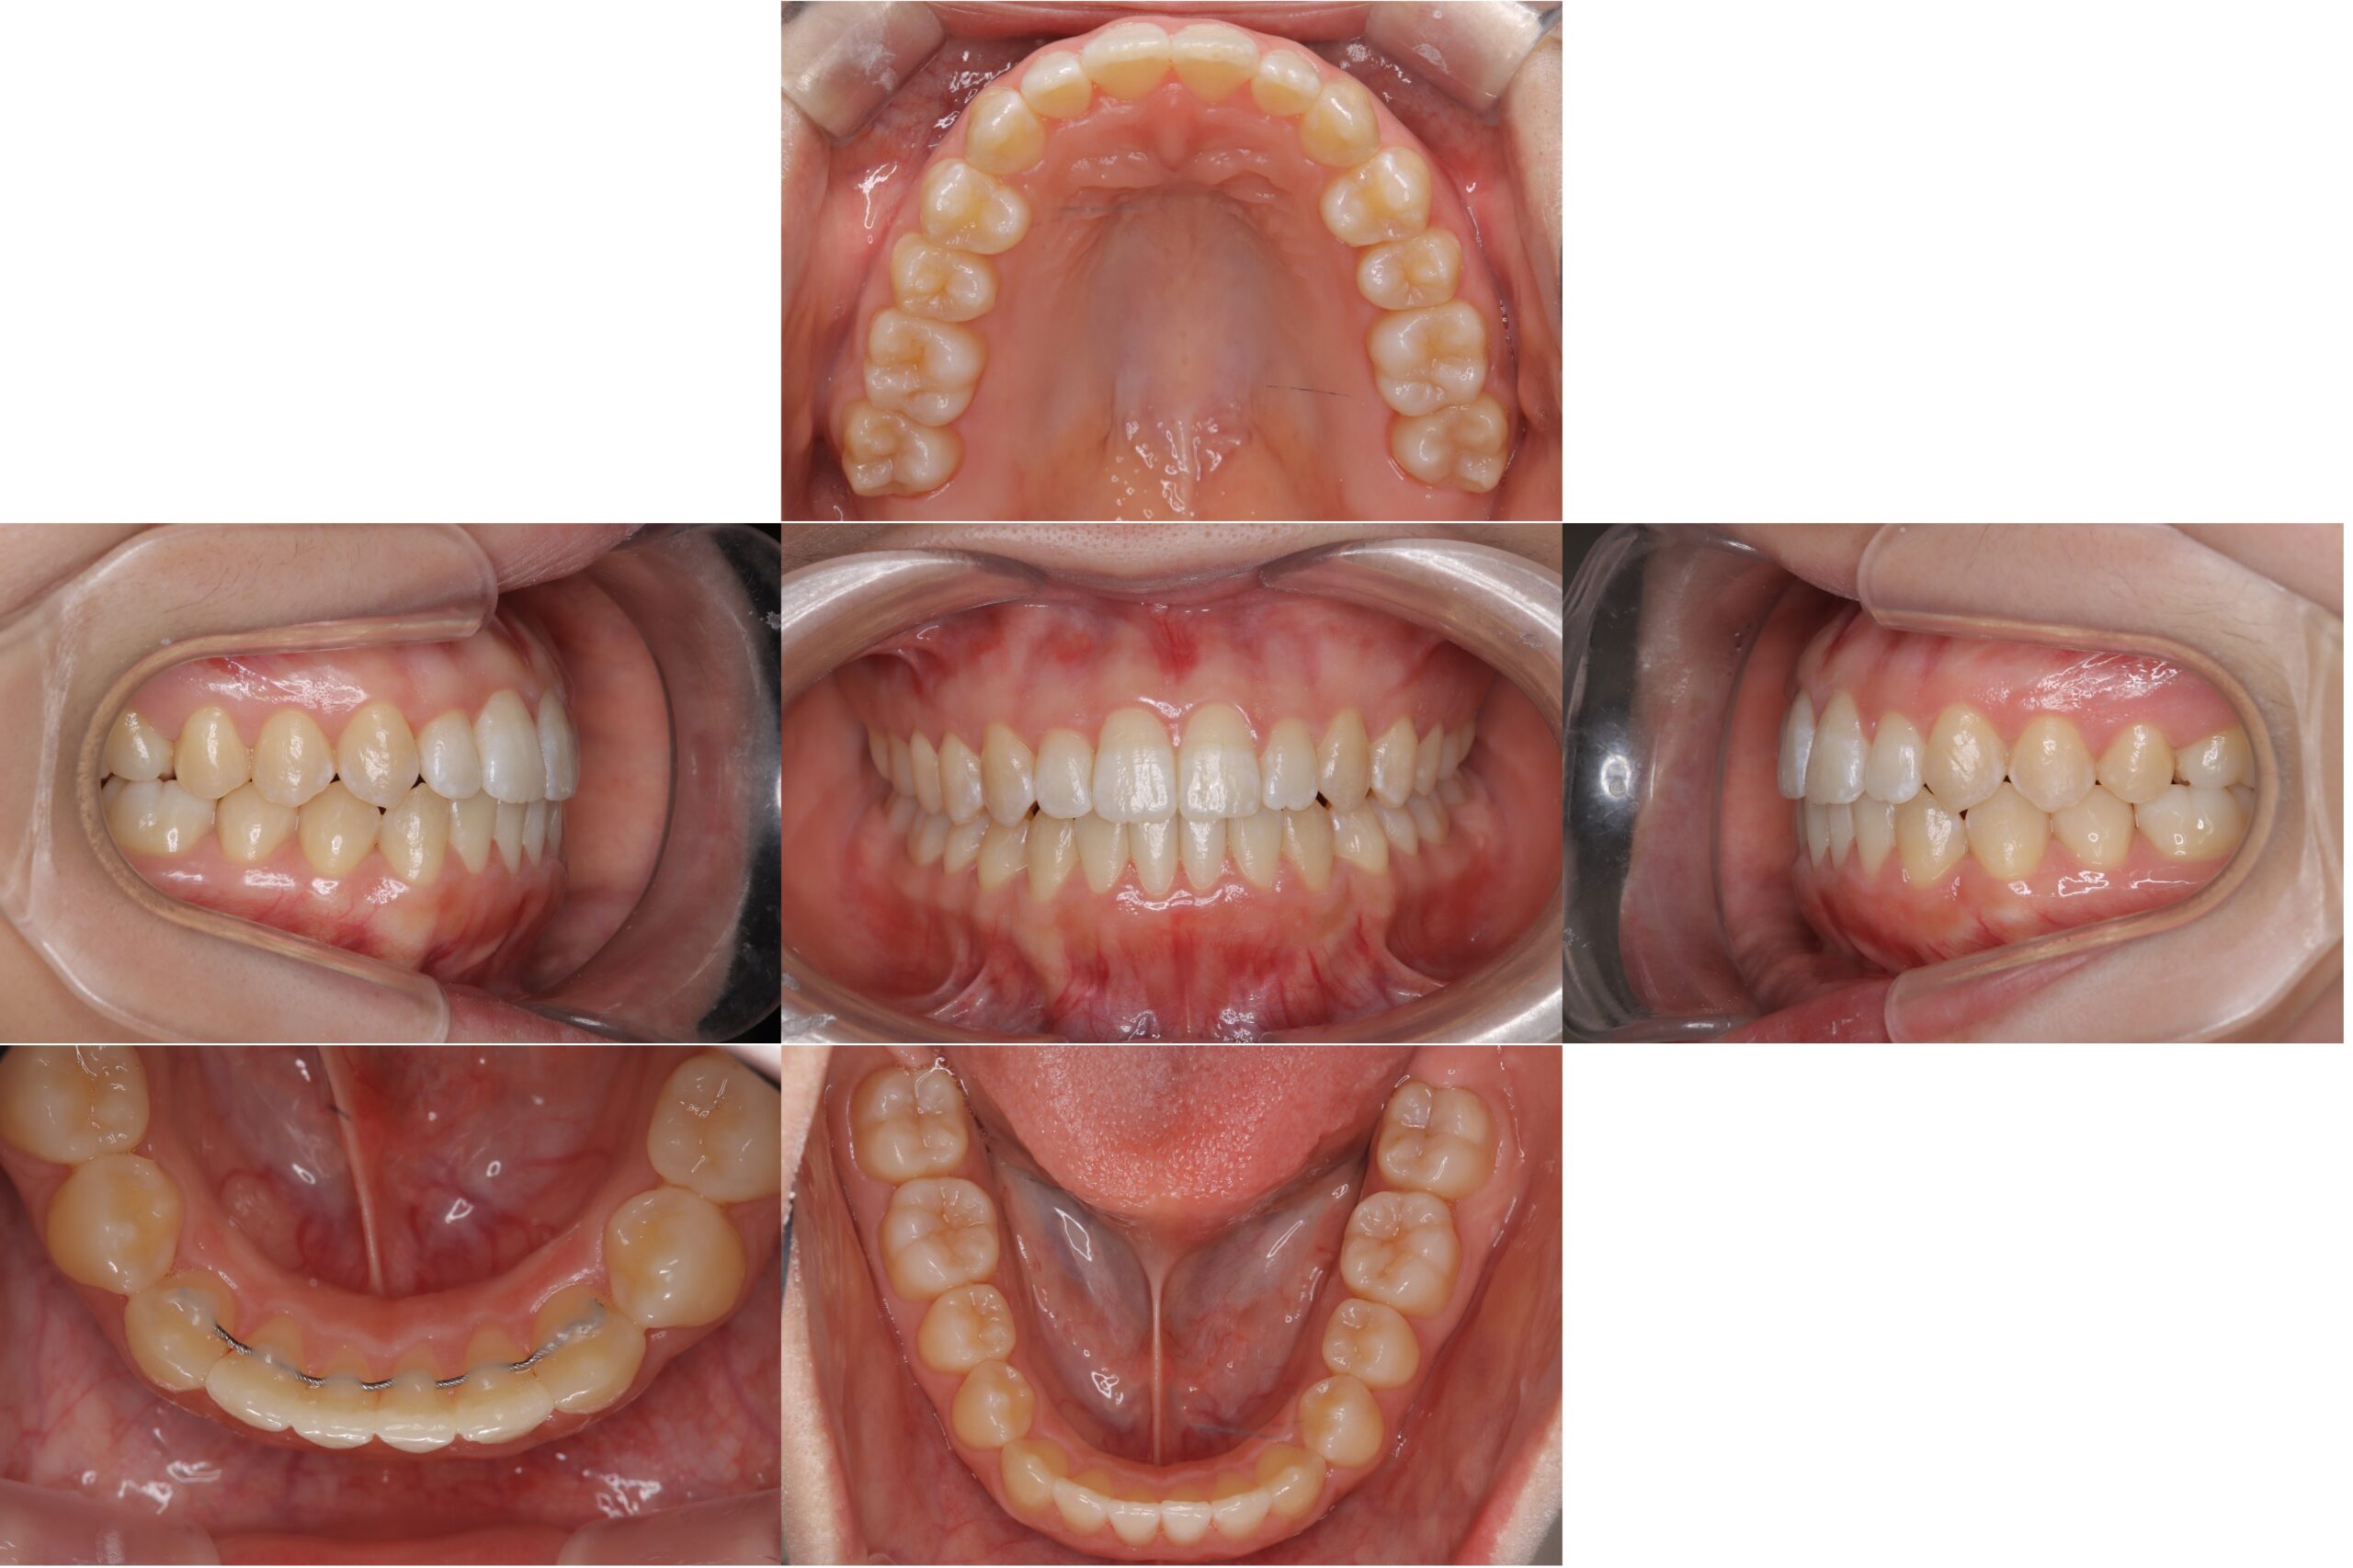

矯正治療

2026-04-16

BEFORE AFTER

インビザラインがたつきを綺麗に

主訴 前歯が出っ張ているところが気になる

期間 約1年

費用 770,000円(税込)

治療内容 インビザライン:コンプリヘンシブパッケージ

治療に伴うリスク マウスピース型矯正装置による治療に関するリスク・副作用<br /> ・口腔内の状態等により適応とならない場合があります<br /> ・十分な治療効果を得るためには、長時間(目安として1日22時間以上)の装着が必要です<br /> ・装着時間および使用状況により、治療計画通りに進行しない可能性があります<br /> ・治療終了後、保定が不十分な場合には後戻りが生じる可能性があります<br /> ・未承認医療機器を使用する場合があり、医薬品副作用被害救済制度の対象外となることがあります<br /> ・治療結果および治療期間には個人差があります<br /> ・本治療は自由診療(保険適用外)です